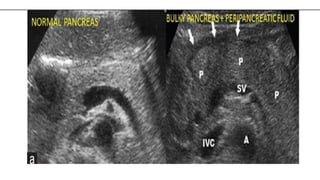

Transverse ultrasound demonstrates

diffuse enlargement of the pancreas ,

which appears abnormally hypoechoic

Transverse ultrasound demonstrates diffuseenlargement of the pancreas , which appears abnormally hypoechoic